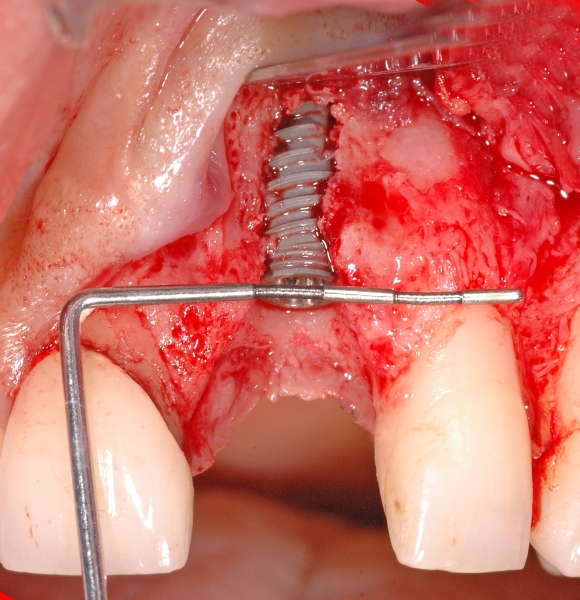

5/18 - Situation after implantation showing a buccal defectGBR together with soft tissue augmentation with mucoderm® and maxresorb® - Dr. S. Scherg

6/18 - Augmentation with maxresorb® and covering with a non-resorbable PTFE membraneGBR together with soft tissue augmentation with mucoderm® and maxresorb® - Dr. S. Scherg